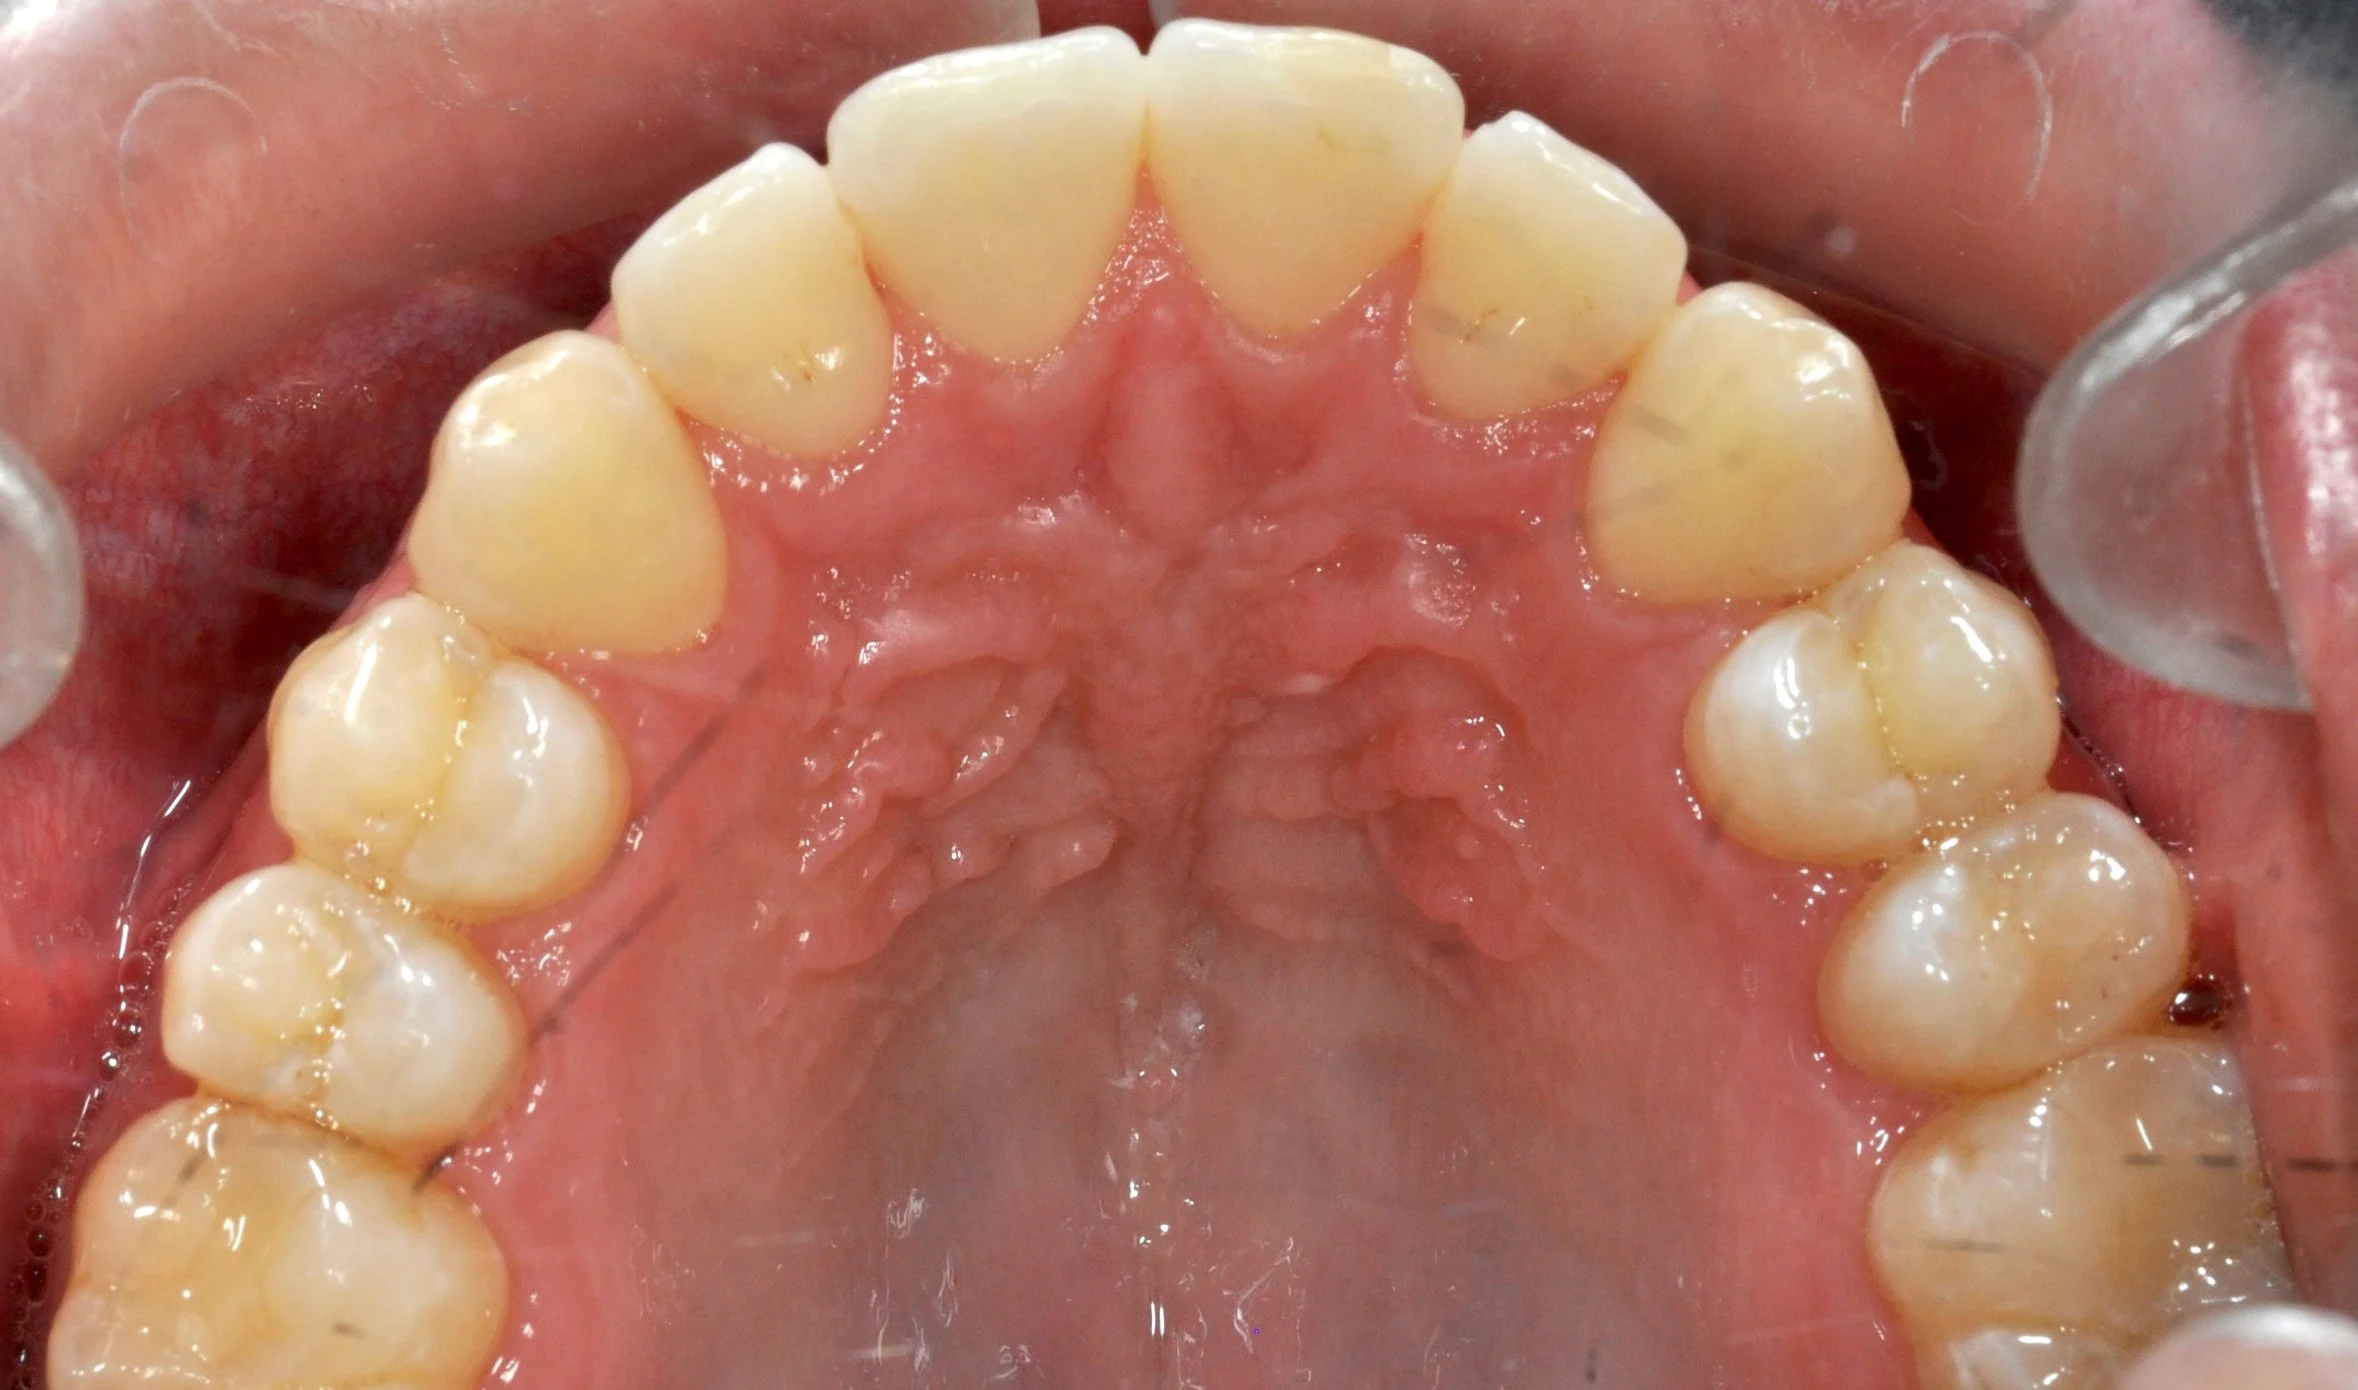

Paziente adulto con importante affollamento dei denti inferiori, arcate strette e tendenza al morso aperto, con difficoltà nel corretto contatto tra i denti superiori e inferiori.

Il trattamento con allineatori trasparenti ha permesso, in circa 18–20 mesi, di riallineare i denti, ampliare le arcate e migliorare la chiusura del morso, ottenendo un risultato stabile, funzionale ed esteticamente armonioso.

PRIMA